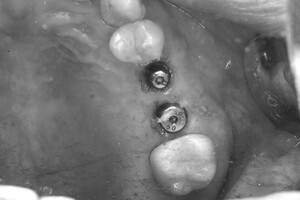

症例写真-2

- Befor

- 途中経過

- After

| 年齢 | 50代・男性 |

| 主訴 | 左上7番 左下5番7番 |

| 治療内容 | ・インプラント埋入 ※1:GBR(骨造成)・・・骨再生誘導法。骨の高さや厚みを人工骨や人工膜などを使用し再生する方法 |

| 治療費 | 合計:1,809,500円(税込) ■内訳 ・左上7番 ・左下5番7番 |

| 治療期間 | 左上7番約1年 左下5番7番約10ヵ月 |

| 治療方針 | 左上7番は昔他院で被せものをしており、被せものの中が歯ぐきの中まで虫歯になっていたため抜歯せざるを得ない状態だった。抜歯と同時に骨造成を行い、骨が出来るまで4ヵ月待ってからインプラントを埋入した。 ※2ポンティック・・・歯のない部分を補うダミーの歯。 |

| 担当者所見 | 元々金属の被せものが多く入っていたため、2次カリエス※3が多かった。今回は金属ではなく、ジルコニアを使用し、2次カリエスにならないよう、患者様にはブラッシング指導とメンテナンスの重要性をお伝えした。 ※3二次カリエス・・・詰め物や被せものを入れた歯が虫歯になること。 |